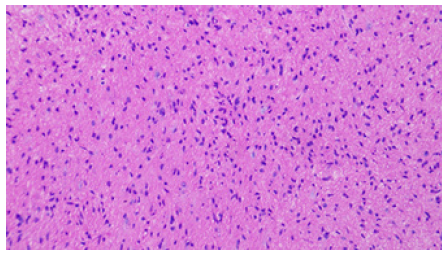

Because of the limited space on the right side, the entry point was chosen on the left frontal incision. After general endotracheal tube anesthesia, the patient was secured in supine position with head on a horse-shaped headrest. Endoscopic Third Ventriculostomy (ETV), Endoscopic Tumor Biopsy (ETB) and Ommaya reservoir insertion were performed successively through the left frontal burr hole (LOTTA Endoscope; Karl Storz, Tuttlingen, Germany) (Figure 3). A catheter was inserted at the opening of the cyst and an Ommaya reservoir was anchored subcutaneously beside the incision. The post-operative course was uneventful. The result of the histopathological examination was low-grade glioma (Figure 4).

Figure 4: The histological diagnosis was low grade glioma (fibrillary astrocytoma) and the immunohistochemistry results revealed Vim (+), GFAP (+), S-100 (+), Olig-2 (+), CD34 (+), H3K27Me3(+), Braf (-), EMA (-),Syn (+), MGMT (+), Ki-67 (+).